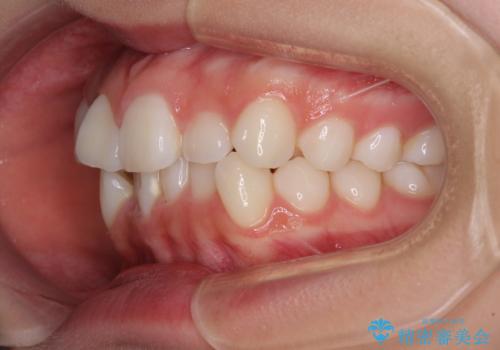

上下の骨格での左右差が小さかったことと、抜歯矯正であったことで、上下正中の位置をきれいに合わせることができました。